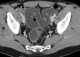

Seminal vesicle calcification

Vas deferens calcification

Calcifications in scrotum

Scrotal calcification